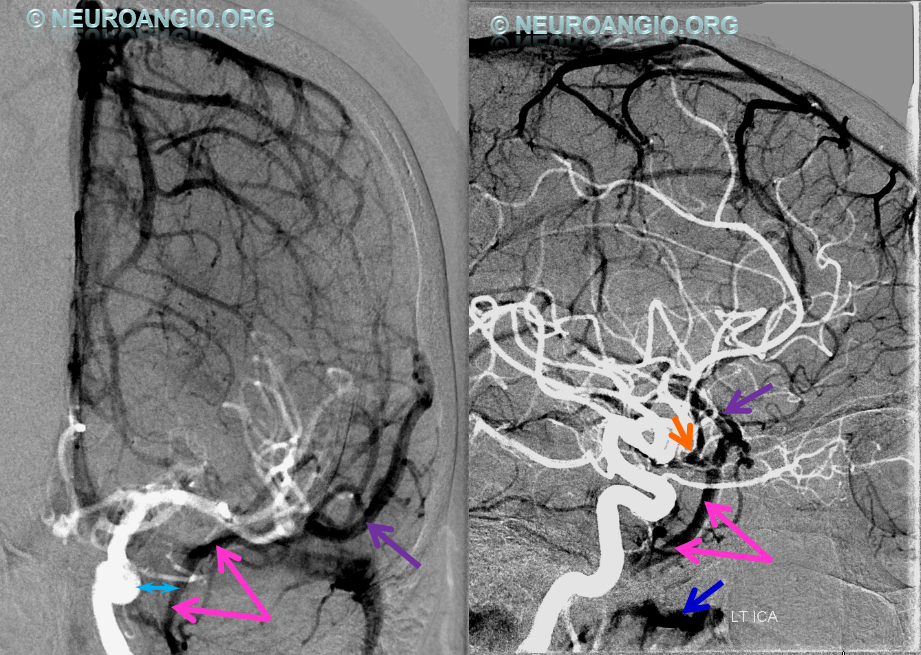

Blue Circle=tumor blush. The superficial Sylvian vein is prominent within the circle and extends over the temporal lobe towards the superior petrosal sinus (dark blue arrow). Labbe=black. No Trolard is seen, various superior cortical veins drain into the SSS. Basal vein=light blue, dominant posterior drainage. Very nice demonstration of the deep venous system tributaries. Anterior Septal vein=bright green, capturing territory of hypoplastic anterior cerebral vein. The inferior sagittal sinus is absent. Thalamostriate vein with large longitudinal caudate vein=yellow. Direct lateral vein=pink. Posterior caudate/splenial veins=brown. A prominent Pericallosal Vein empties into a large inferior sagittal sinus. Also note hypoplasia of the superior sagittal sinus proximal to a large superior frontal convexity tributary.